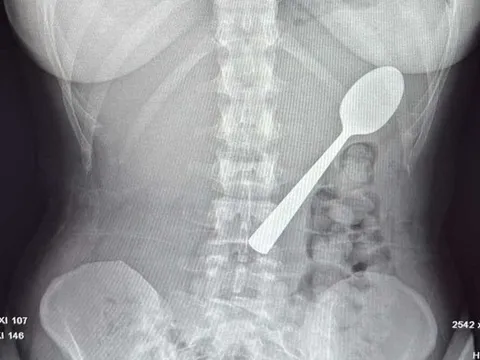

Đau quặn bụng dữ dội, người phụ nữ 55 tuổi phát hiện bí mật đáng sợĐỌC NGAY